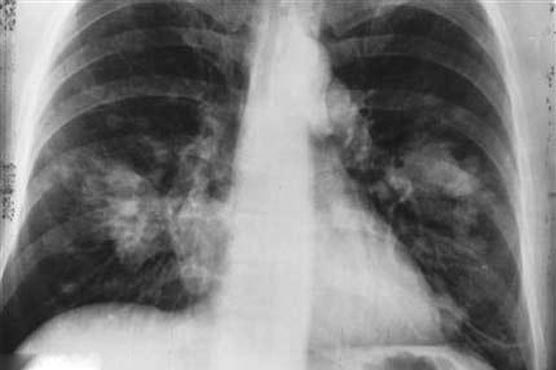

Summary Drug-resistant TB is more difficult and costly than normal TB to treat.

Scientists have found alarming levels of the lung disease tuberculosis in Africa, Asia, Europe and Latin America that are resistant to up to four powerful antibiotic drugs.In a large international study published in the Lancet medical journal on Thursday, researchers found rates of both multi drug-resistant TB (MDR-TB) and extensively drug-resistant TB (XDR-TB) were higher than previously thought and were threatening global efforts to curb the spread of the disease.Most international recommendations for TB control have been developed for MDR-TB prevalence of up to around 5 percent. Yet now we face prevalence up to 10 times higher in some places, where almost half of the patients ... are transmitting MDR strains, Sven Hoffner of the Swedish Institute for Communicable Disease Control, said in a commentary on the study.TB is already a worldwide pandemic that in 2010 infected 8.8 million people and killed 1.4 million of them.Drug-resistant TB is more difficult and costly than normal TB to treat, and is more often fatal.MDR-TB is resistant to at least two first-line drugs - isoniazid and rifampicin - while XDR-TB is resistant to those two drugs as well as a powerful antibiotic type called a fluoroquinolone and a second-line injectable antibiotic.Treating even normal TB is a long process, with patients needing to take a cocktail of powerful antibiotics for six months. Many patients fail to correctly complete treatment, a factor which has fuelled a rise in the drug-resistant forms.Researchers who studied rates of the disease in Estonia, Latvia, Peru, the Philippines, Russia, South Africa, South Korea, and Thailand found that almost 44 percent of cases of MDR TB were also resistant to at least one second-line drug.